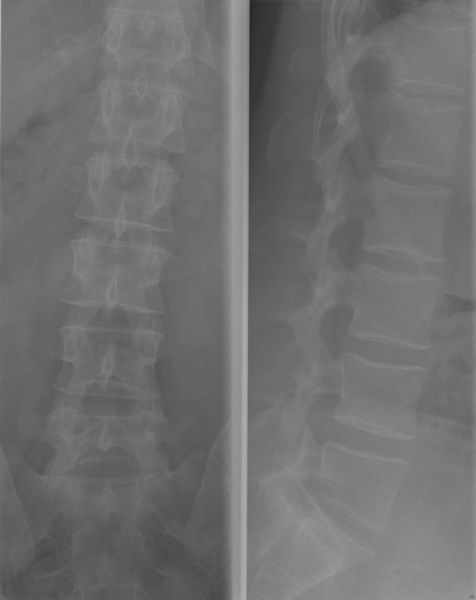

Dorsale wervelzuil